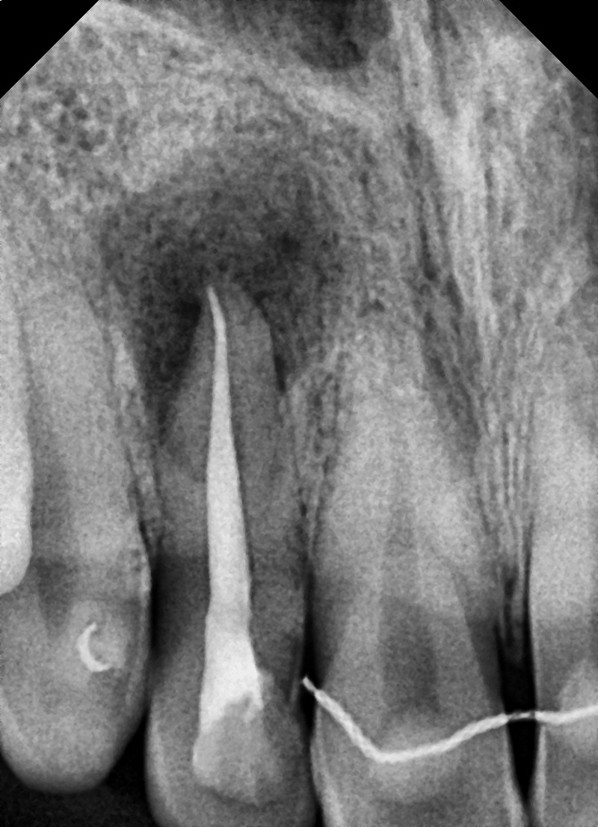

고름주머니 즉 치근단농양은

흔히 신경 괴사, 충치 진행, 외상 등

치근단 염증에서 발생합니다.

해당 환자분도

단순히 염증 크기만 보고

발치를 결정한 것으로 보였지만,

실제 원인은

충치로 인한 신경염증이었습니다.

따라서 저는

다음과 같은 치료계획을 세웠습니다.

- 신경치료(근관치료)

- 염증 조절

- 최종 크라운 복원